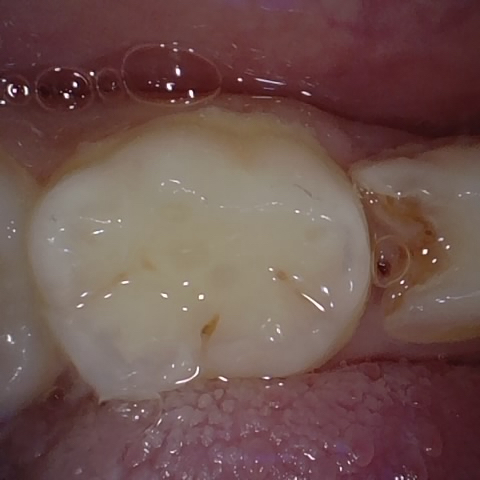

Annotated as "Good"